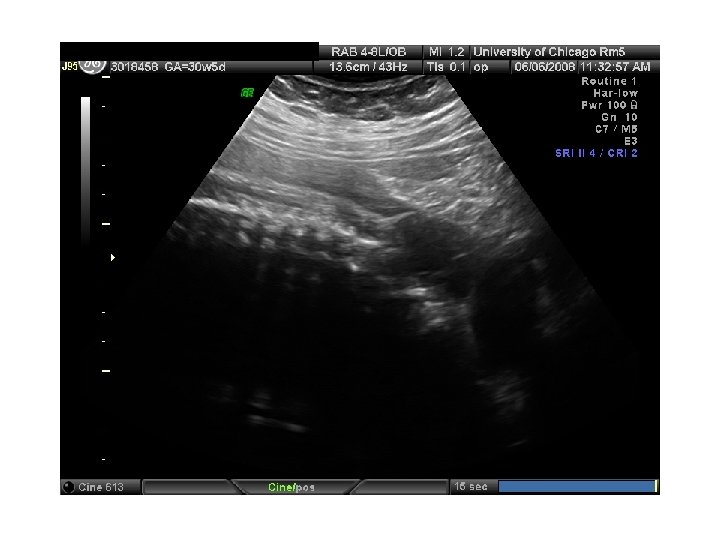

QUIZ What is Your Diagnosis? Case: Patient J. F. 30 years old, at 32 week gestation. Presented with the following pictures.

Answer: a) Trisomy 21 b) Non-immune Hydops c) Paravo virus Infection